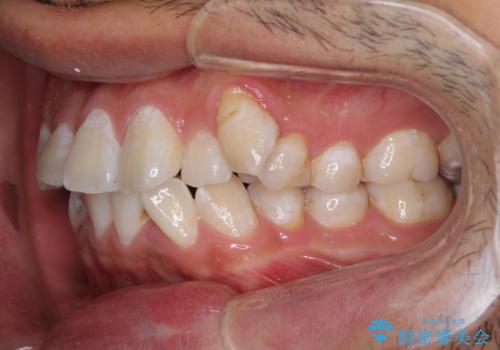

叢生が強く、奥歯の咬合も左右差が大きかったため、上下左右4本を抜歯して、ワイヤー矯正を行うこととしました。

奥歯の咬み合わせを改善したいため、治療期間が長くなりましたが、患者様には辛抱強くお付き合いいただきました。

上下の正中を合わせることもでき、患者様には大変満足していただきました。